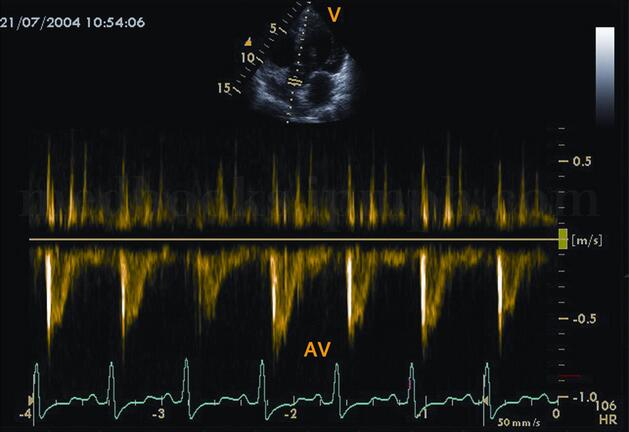

(1)各瓣口血流速度降低(图2‐1‐190)。

图2‐1‐190 主动脉瓣口血流峰值流速(Vmax)、流速积分(VTI)均减低